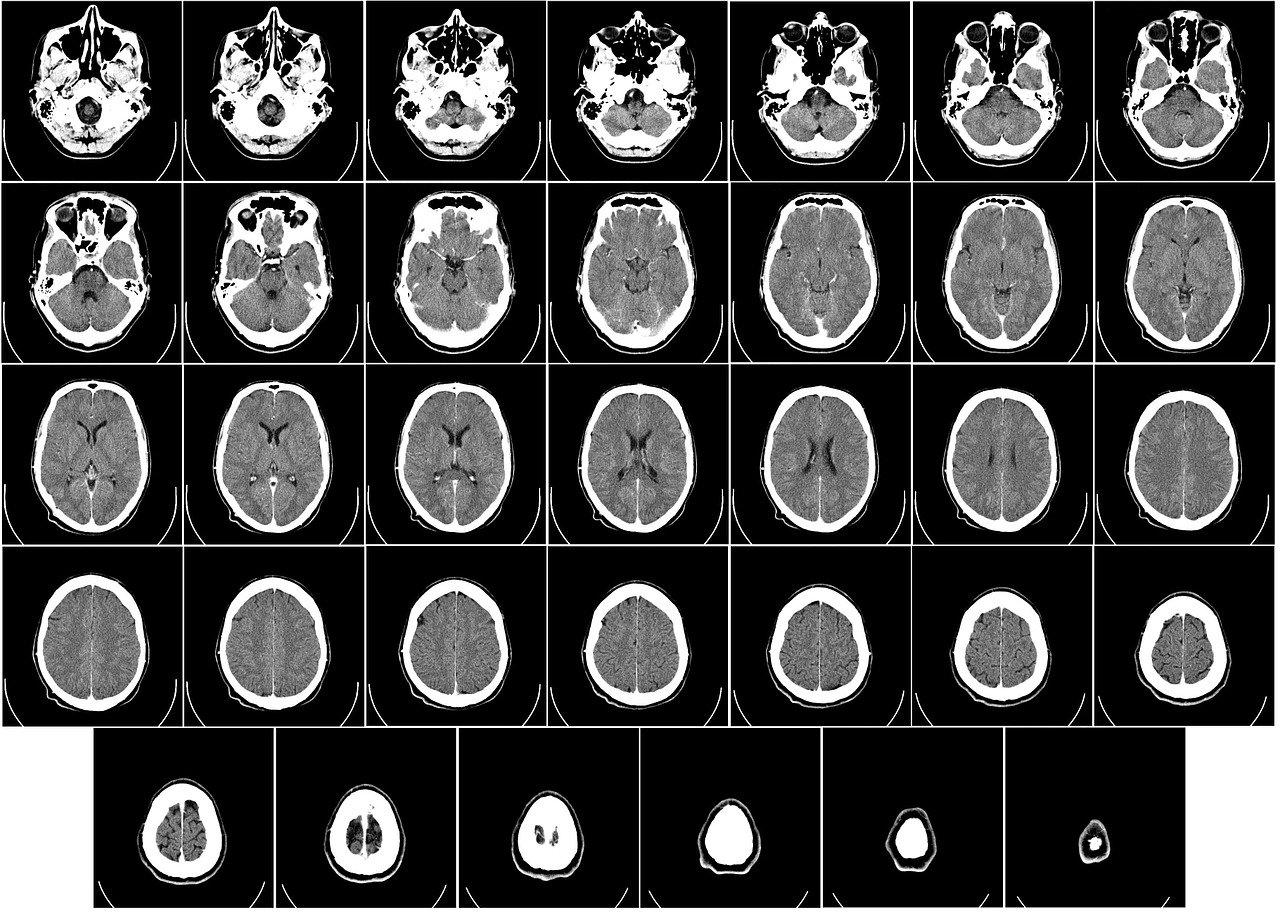

[모야모야병] CT 및 디지털 감산 혈관조영술(DSA)

모야모야병은 내경동맥 말단부 및 그 분지에서 진행성 협착이 발생하여 뇌혈류가 감소하고, 그 보상 작용으로 미세한 우회 혈관(신생혈관)이 형성되는 희귀 뇌혈관 질환입니다. 이러한 혈관 변화는 뇌경색, 뇌출혈 등 심각한 합병증을 유발할 수 있기 때문에, 정확한 영상 진단은 치료 결정과 예후 평가에 매우 중요합니다. 모야모야병의 진단에는 여러 영상 기법이 활용되지만, 그 중 CT와 DSA는 각각의 특징과 장점을 바탕으로 중요한 역할을 수행하고 있습니다. CT(컴퓨터 단층 촬영) 영상 검사 CT의 기본 원리 및 역할CT는 X-선을 이용해 신체를 단면별로 촬영하는 영상 기법입니다. 다양한 각도에서 촬영한 X선 데이터를 컴퓨터를 통해 재구성함으로써, 뇌의 구조와 병변 부위를 상세하게 확인할 수 있습니다. 모야모야병..